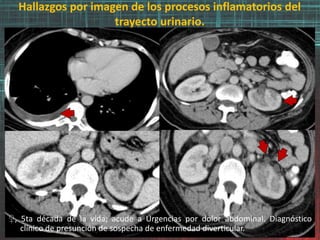

♀, 5ta década de la vida; acude a Urgencias por dolor abdominal. Diagnóstico

clínico de presunción de sospecha de enfermedad diverticular.